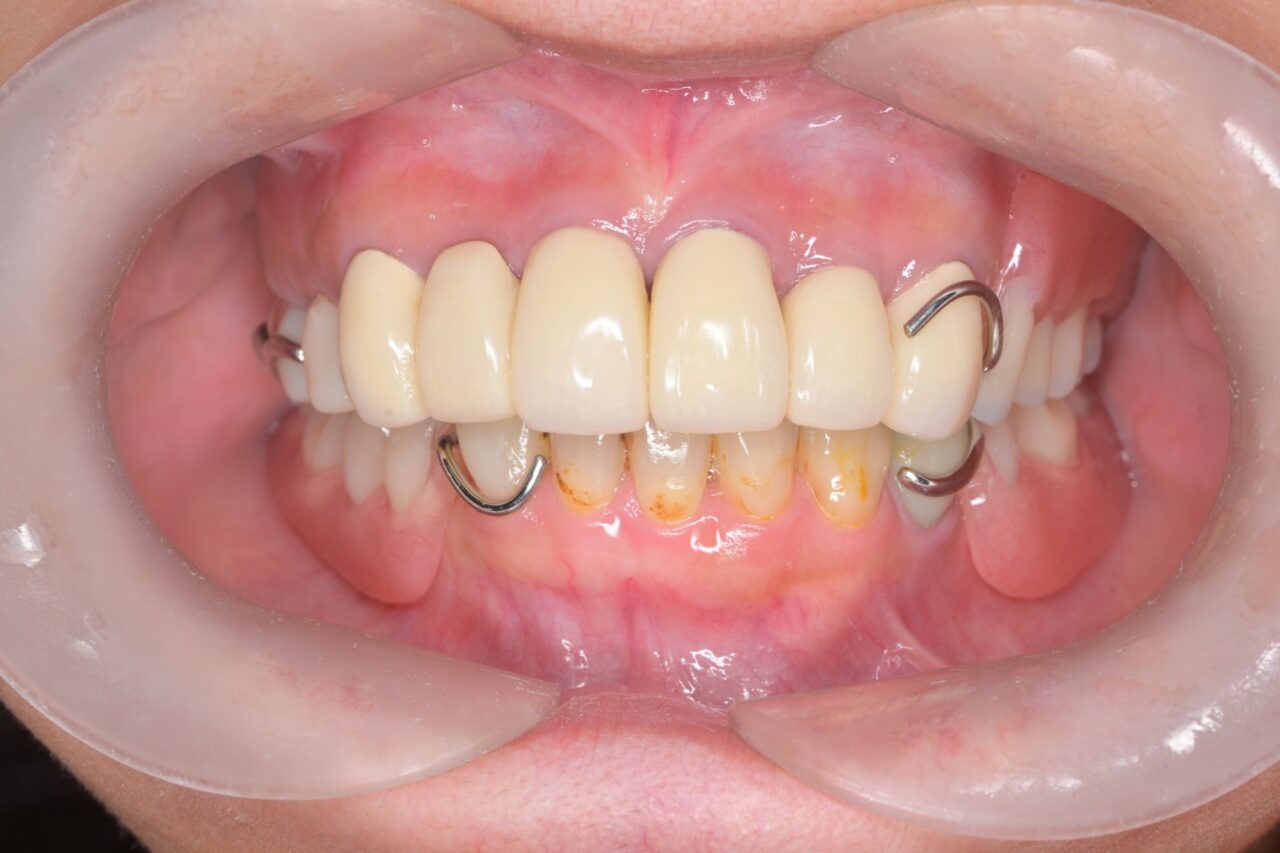

正面

上の歯はフロスが通るように1本ずつ単冠で治療しています。

歯周病で歯茎がロスしていましたので歯が長く見えています。